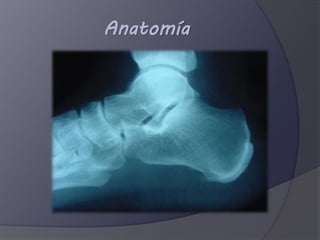

El documento describe la anatomía y las fracturas del hueso calcáneo. Explica que el calcáneo es el mayor y más fuerte de los huesos del pie y transmite la mayor parte del peso corporal. También clasifica las fracturas del calcáneo, dividiéndolas en extraarticulares, que representan el 25% de los casos, e intraarticulares, que son el 75% más común y pueden ser por hundimiento articular o en forma de lengua.